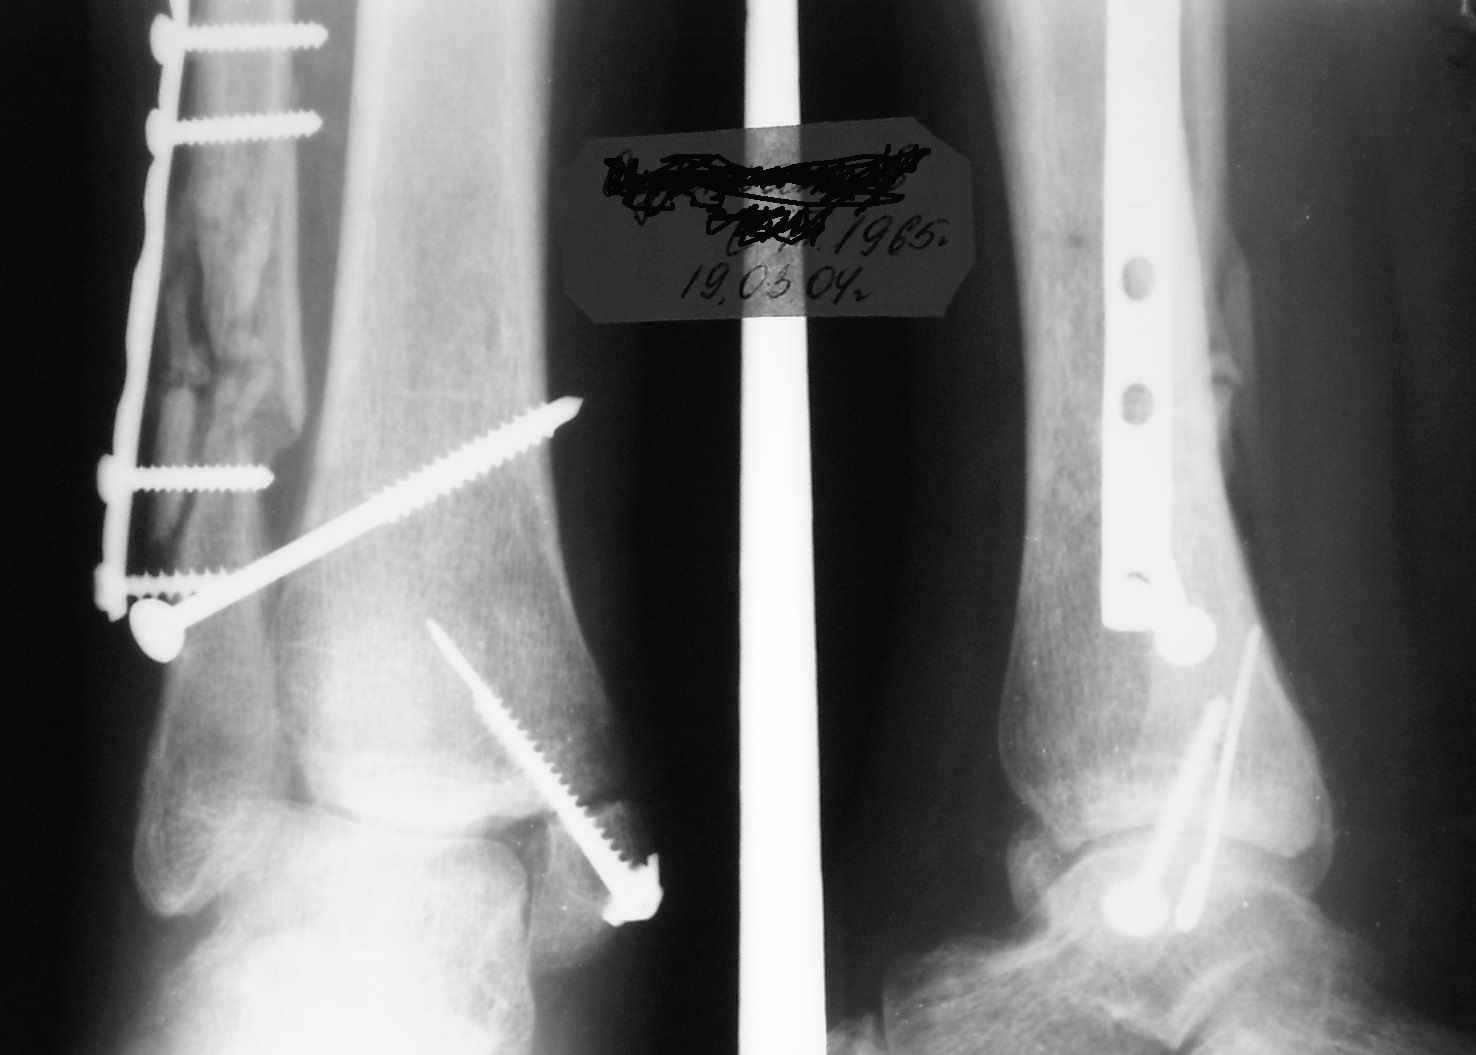

15 ноября прямой

|

15 ноября боковой

15 ноября трехчетвертной

Риторический вопрос - в каком руководстве рекомендован такой способ остеосинтеза наружной лодыжки?

Очевидно, такой результат операции был запрограммирован. При невосстановленной длине и практически нефиксированной малоберцовой кости (этот кортикальный винт - как карандаш в стакане), при неустраненном подвывихе, невправленной и тоже нефиксированной внутренней лодыжке нет стабильной вилки сустава. Если такую операцию сделать даже сразу, а не через 4 месяца, то результат ожидаем

Вариант с артродезом уже обсудили. Хотя, после увиденых снимков, пессимизм насчет восстановительной операции у меня, например, несколько уменьшился. Особенного уж какого-то остеопороза не видно даже на январских снимках. Можно черед мини-доступы убрать винты, аппаратом вправить малоберцовую кость, устранить подвывих стопы. Ну а дальше фиксировать малоберцовую пластиной сзади. А может, и напряженной Y-спицей попробовать - Анатолий Федорович, как Вы полагаете? Внутреннюю - то, что осталось, если уже не получится сделать спицами и проволокой, то что-то типа пластики дельтовидной связки. А может, и не трогать ее вовсе... В общем, выбор непростой,

много факторов надо взвесить.

Если до сих ничего не сделано, с артродезом сустава в данный момент я бы повременил, на выставленных январских снимках хорошо сохранившийся сустав, а в "мортиз" (трехчетвертной) и на боковых снимках не менее 5 мм укорочение малоберцовой кости. Косые переломы лучше фиксировать пластинами, как то мы разбирали случай, где было отмечено, что это закон "таранная кость всегда следует за малоберцовой".